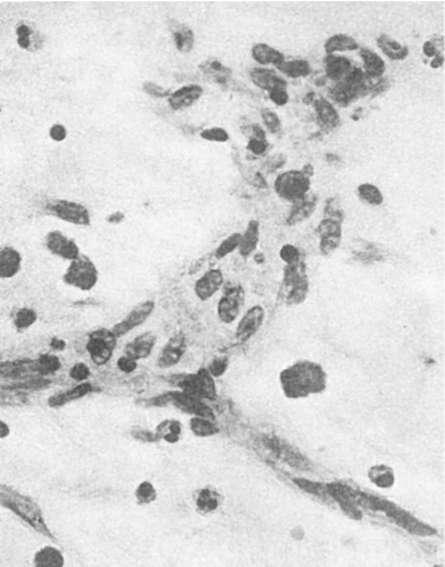

Микрососуды обладают большей способностью регенерировать, чем крупные сосуды. Новообразование микрососудов может происходить путем почкования или аутогенно. При регенерации сосудов путем почкования (рис. 82) в их стенке появляются боковые выпячивания за счет усиленно делящихся эндотелиальных клеток (ангиобласты). Образуются тяжи из эндотелия, в которых возникают просветы и в них поступает кровь или лимфа из

«материнского» сосуда. Другие элементы: сосудистой стенки образуются за счет дифференцировки эндотелия и окружающих сосуд соединительнотканных клеток, В сосудистую стенку врастают нервные волокна из предсуществующих нервов. Аутогенное новообразование сосудов состоит в том, что в соединительной ткани появляются очаги недифференцированных клеток. В этих очагах возникают щели, в которые открываются предсуществующие капилляры и изливается кровь. Молодые клетки соединительной ткани, дифференцируясь, образуют эндотелиальную выстилку и другие элементы стенки сосуда.

Рис. 82. Регенерация

сосудов путем почкования